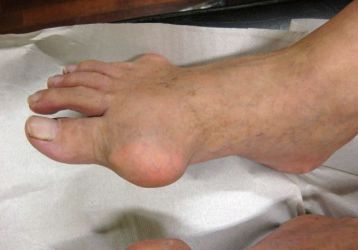

• Подагра. Это хроническая патология, характеризующаяся повышенным количеством мочевой кислоты в крови. Далее, она превращается в соль и откладывается в суставах. Именно она вызывает воспаление суставов.

Шишки на суставах: причины, симптомы, разновидности

Что содержится внутри шишек суставов. Почему они появляются и какие способы удаления существуют. Как избежать появления.